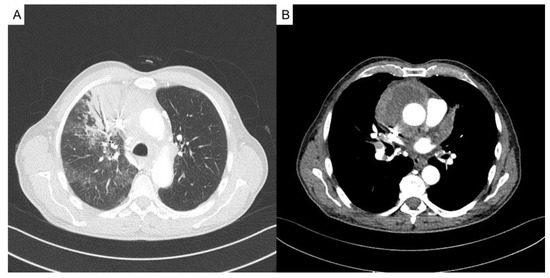

Introduction: Hypertension is occasionally associated with congenital hydronephrosis. Case report: The authors report a four-month-old boy with severe left congenital hydronephrosis and transient hypertension triggered by his first urinary tract infe...